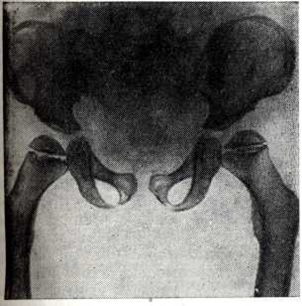

Заболевание характеризуется генерализованным симметричным поражением эпифизов костей. Они уплощены и увеличены. Метадиафизарные отделы длинных и коротких трубчатых костей укорочены и утолщены. Типичной является вальгусная деформация проксимальных отделов бедренных костей (рисунок 3). Плоские кости деформированы, утолщены, суставные впадины уплощены. Ребра также утолщены, передние концы их булавовидно расширены. Шейки рёбер остаются нормальными. Межрёберные промежутки сужены. Позвоночник всегда поражён, имеют место платиспондилия и угловой кифоз в нижнегрудном и верхнепоясничном отделе (рисунок 4). Патогномоничным является недоразвитие передне-верхнего угла тел позвонков, обычно ThXII или LI-II. Межпозвонковые пространства не сужены. Имеется диспропорция в развитии лицевого и мозгового черепа. Основание черепа укорочено. Турецкое седло уплощено, удлинено, передние клиновидные отростки недоразвиты. Кости лицевой части черепа, особенно верхняя челюсть и носовые кости, недоразвиты. Задерживается пневматизация придаточных пазух носа. Изменяются темпы и последовательность окостенения, остеогенез происходит асимметрично.

Рис. 3. | ||